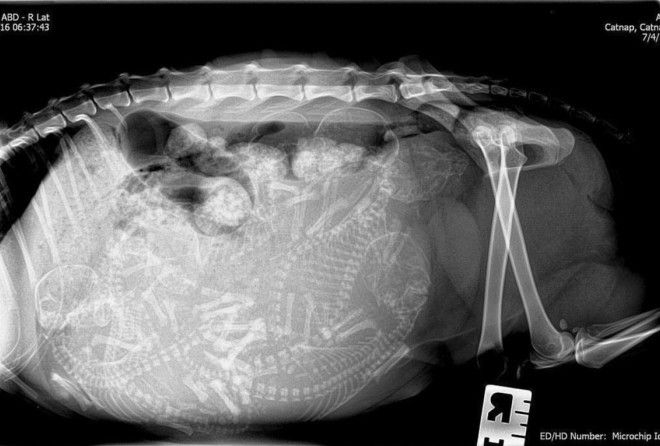

3. Беременная кошка